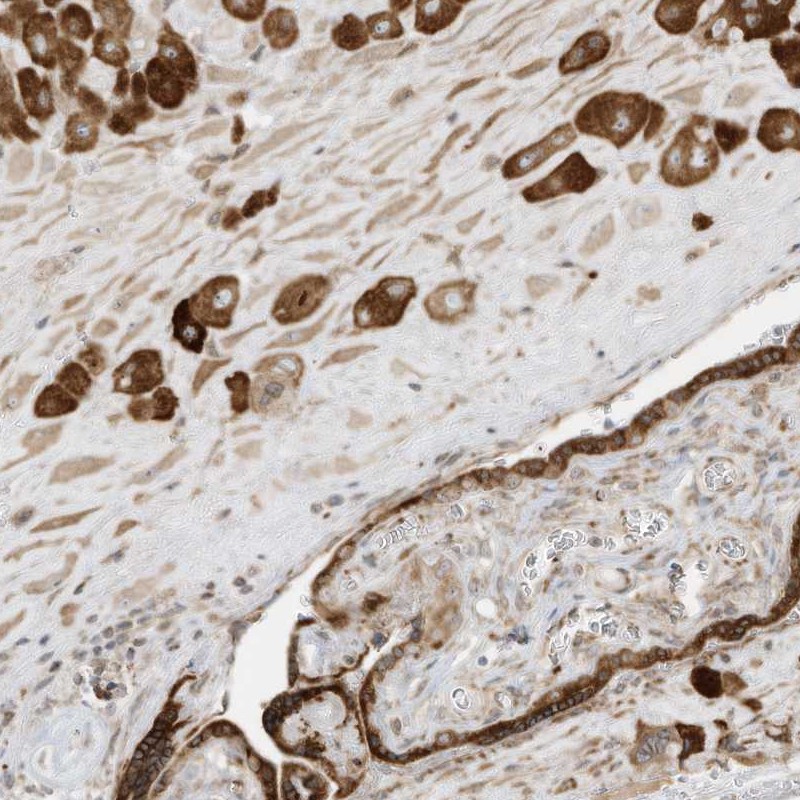

Immunohistochemical staining of human placenta shows strong cytoplasmic positivity in trophoblastic cells and decidual cells.